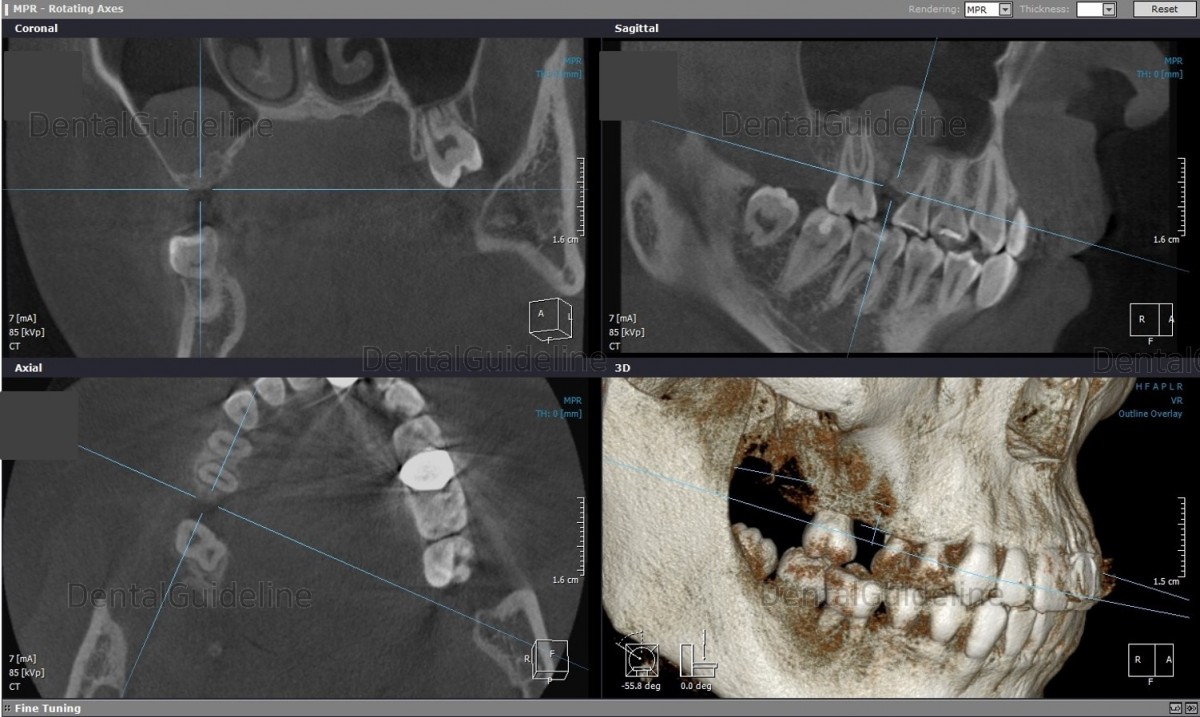

1. The missing 1st molar space should be regained for the

implant-supported crown.

2. A cyst-like appearance in the maxillary sinus was observed on CT.